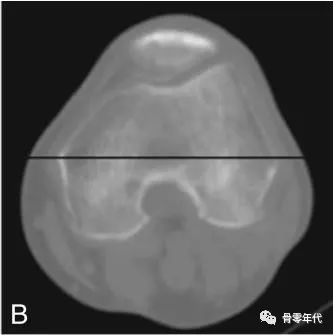

髋臼杯前倾角(C)定义为在矢状面上测量的前倾角